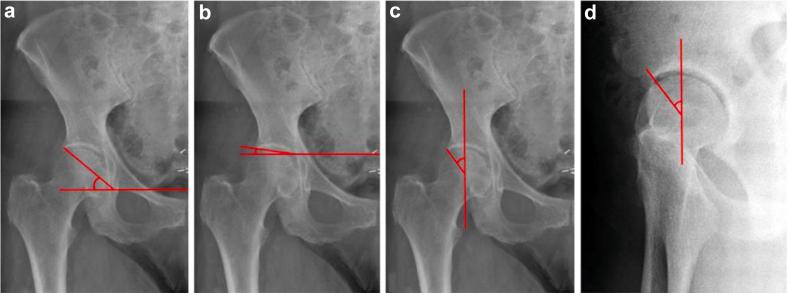

Anteroposterior pelvis radiographs of skeletally mature patients from 2015 were reviewed. Studies with fractures or implants were excluded. Films were read by 2 orthopedic surgeons and a radiologist 3 times each, 8 weeks apart. The SI, Sharp's Angle (SA), and lateral center edge angle (LCEA) were recorded. Pearson intraclass correlation coefficients with 95% confidence intervals were calculated. The SI was then compared to the SA and LCEA to preliminarily assess diagnostic accuracy.

回顾了2015年骨骼成熟患者的骨盆前后位X线片。排除有骨折或植入物的研究。由2名骨科医生和1名放射科医生对X线片进行3次阅片,每次阅片间隔8周。记录SI、夏普角(SA)和外侧中心边缘角(LCEA)。计算具有95%置信区间的Pearson组内相关系数。然后将SI与SA和LCEA进行比较,以初步评估诊断准确性。